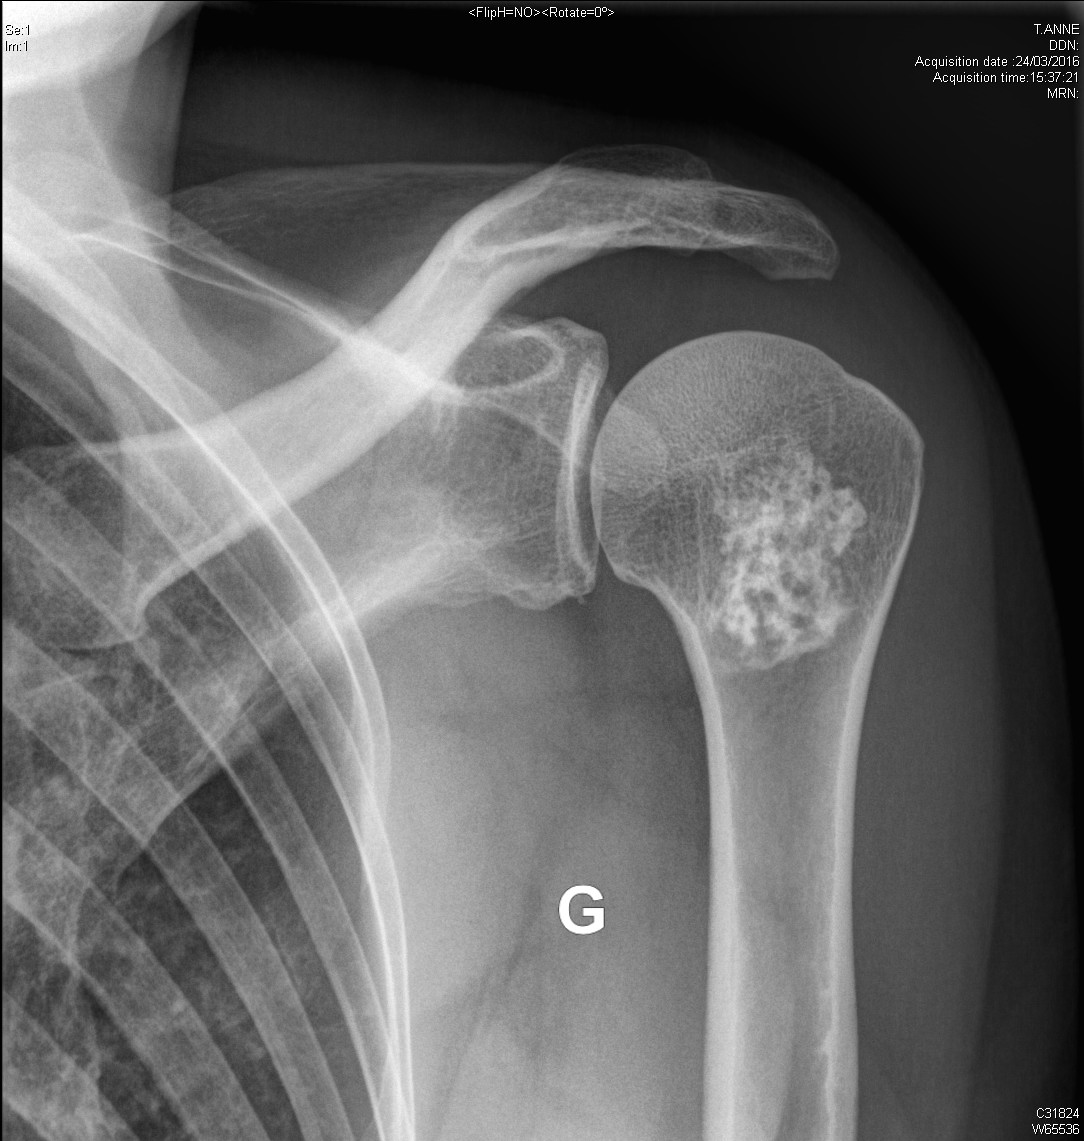

Ostéochondrome de l'épaule